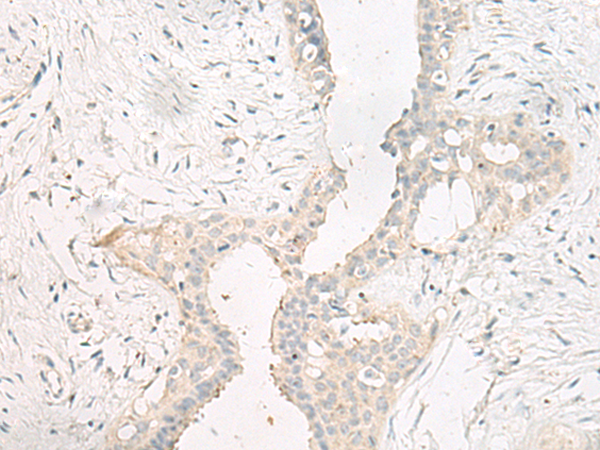

IHC positive control: |

Human cervical cancer and Human breast cancer |

IHC Recommend dilution: |

20-100 |